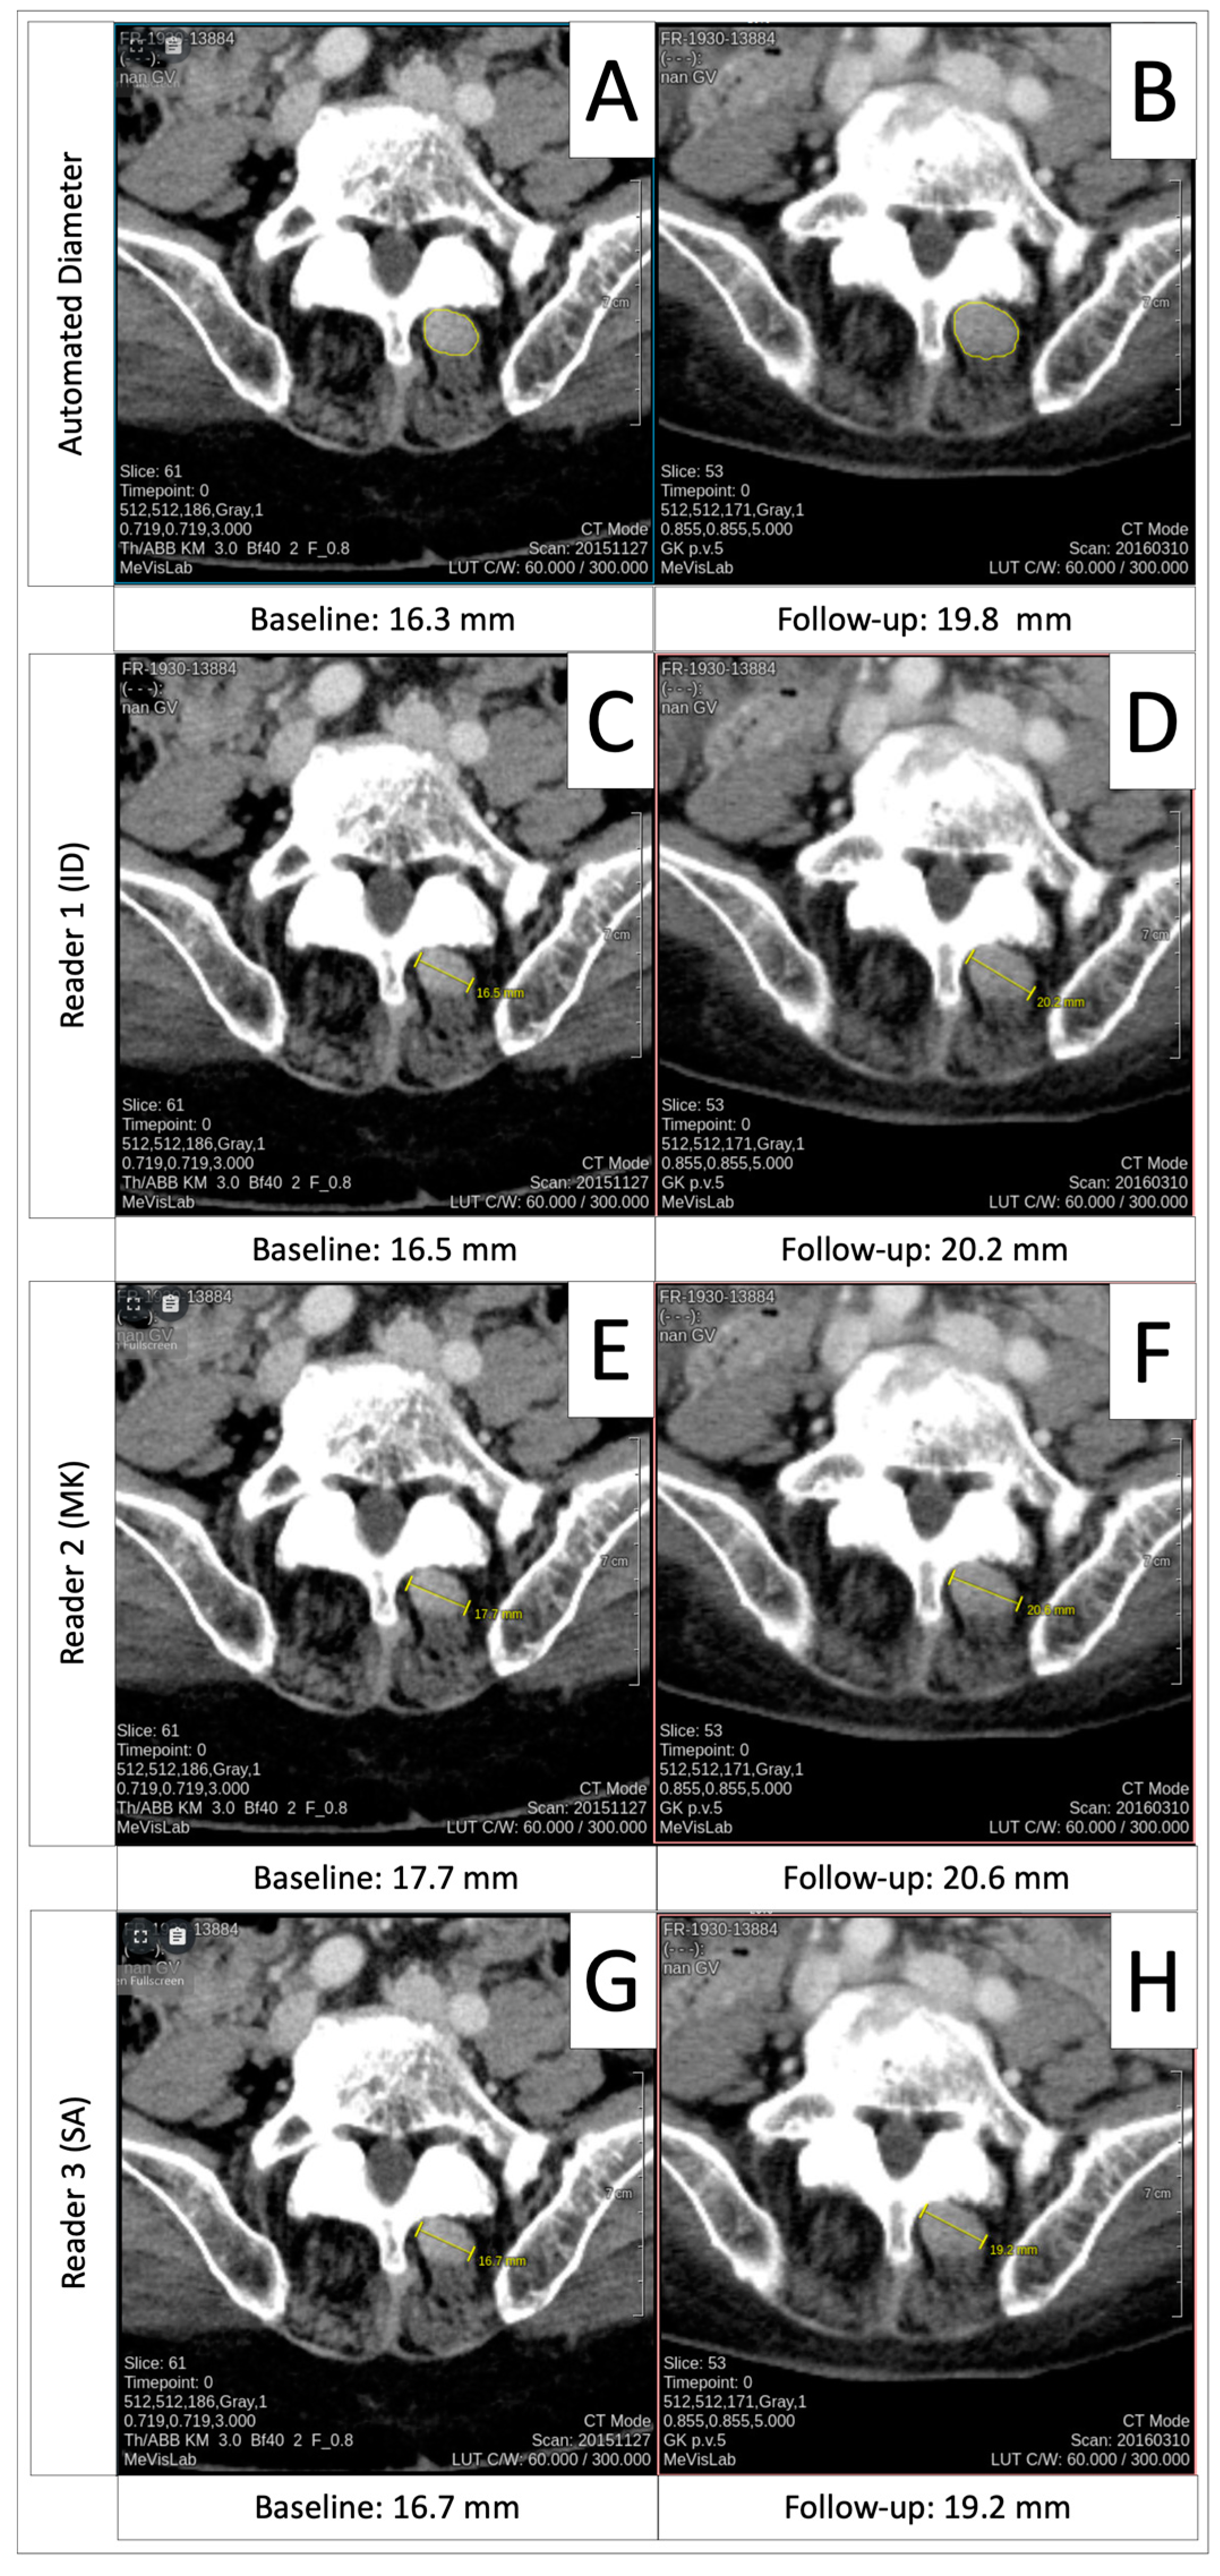

3.4. Comparison of Automated Diameters to Manual Measurements

3.6. Progressive Disease Timepoint Response Deviation